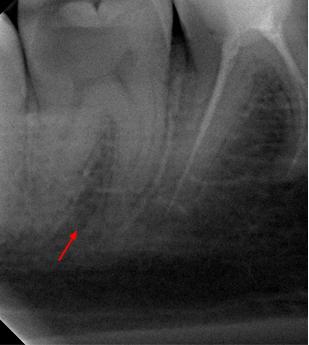

Пациентка 28 лет обратилась с жалобами на приступообразную ночную боль в области нижней челюсти справа.

На жевательной поверхности 47 зуба глубокая кариозная полость в пределах околопульпарного дентина, пульповая камера не вскрыта, зондирование болезненное, перкуссия безболезненная, холодовой тест резко болезненный, после удаления раздражителя болевая реакция продолжается в течении 20-ти секунд.

Диагноз: необратимый пульпит 47-го зуба.

На рентгенологических снимках представлена картина до лечения, диагностический снимок и конечный результат.